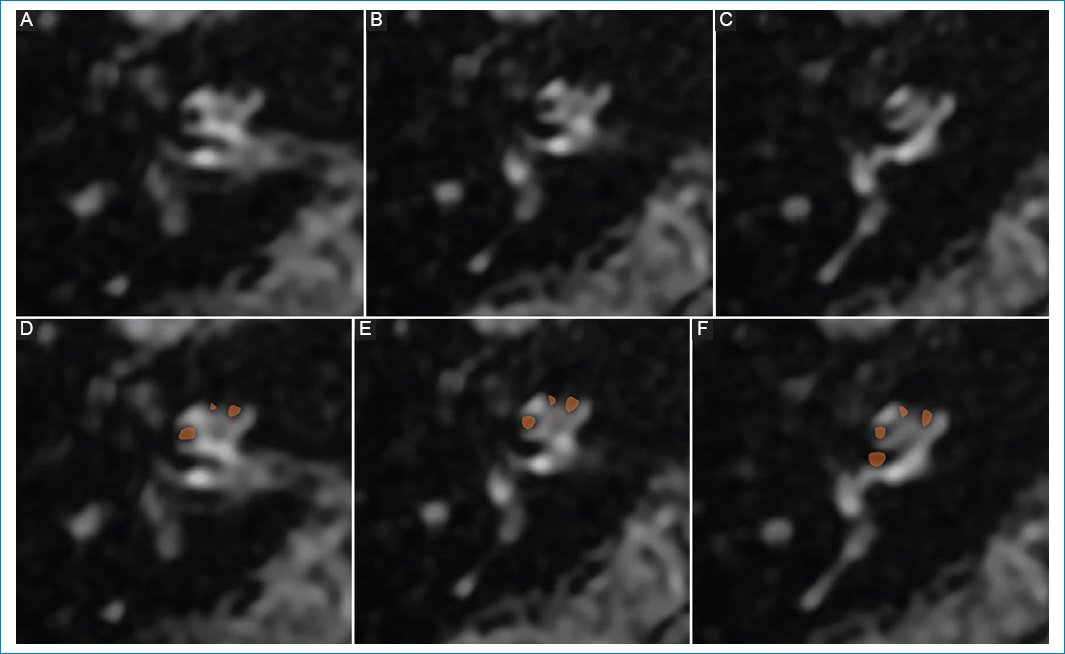

Varón de 76 años que presenta hipoacusia del oído izquierdo y vértigo de un año de evolución. No estaba medicado. En la RM con protocolo de hidrops se evidenció una escala vestibular completamente obliterada debido a la distensión del conducto coclear, que se interpretó como hidrops coclear de grado II (Fig. 4).

Figura 4. (A, B y C) Hidrops coclear de grado II: dilatación en banda de la escala media, vistas de superior a inferior; representación esquemática en D, E y F.